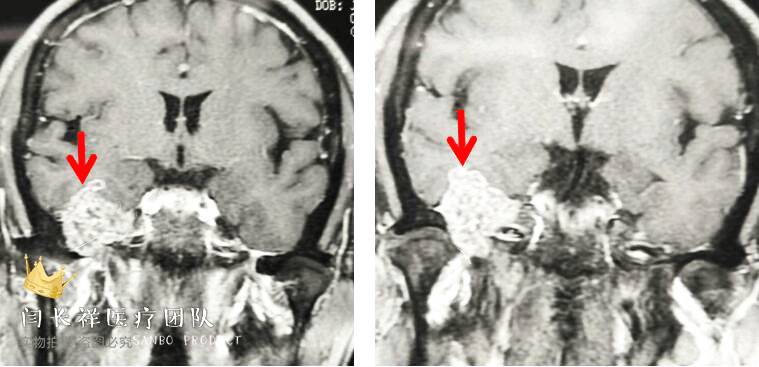

中颅窝-颞下窝占位

术前冠位CT示右侧中颅窝、颞下窝、翼腭窝占位,病灶呈稍高密度。

术前矢状位CT。

术前冠位CT骨窗像示右侧中颅窝底骨质被肿瘤侵蚀破坏。